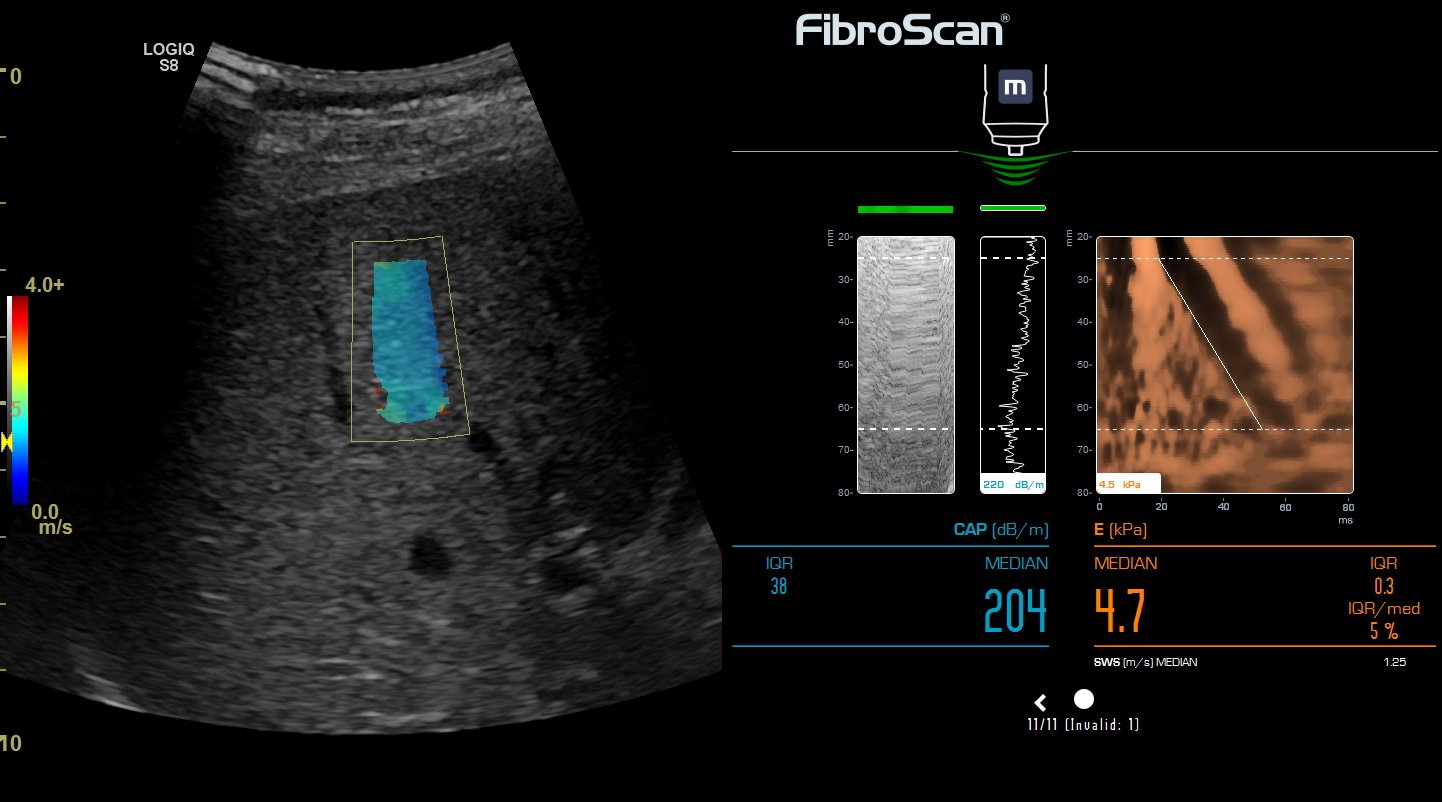

Фиброскан — это современный метод диагностики, который позволяет точно оценить степень фиброза печени с помощью транзиентной эластографии. Этот метод неинвазивен и помогает своевременно выявлять заболевания, такие как цирроз, гепатит и жировой гепатоз, без необходимости в биопсии. В этой статье вы найдете подробную информацию о процедуре, ее преимуществах и советы по подготовке к обследованию.

Эластография печени сдвиговой волной. Диагностика фиброза печени.

FibroScan, or elastography for liver stiffness, fibrosis, method, analysis

Эластометрия печени. Покажет то, что не видно на УЗИ и в анализах.

Эластометрия